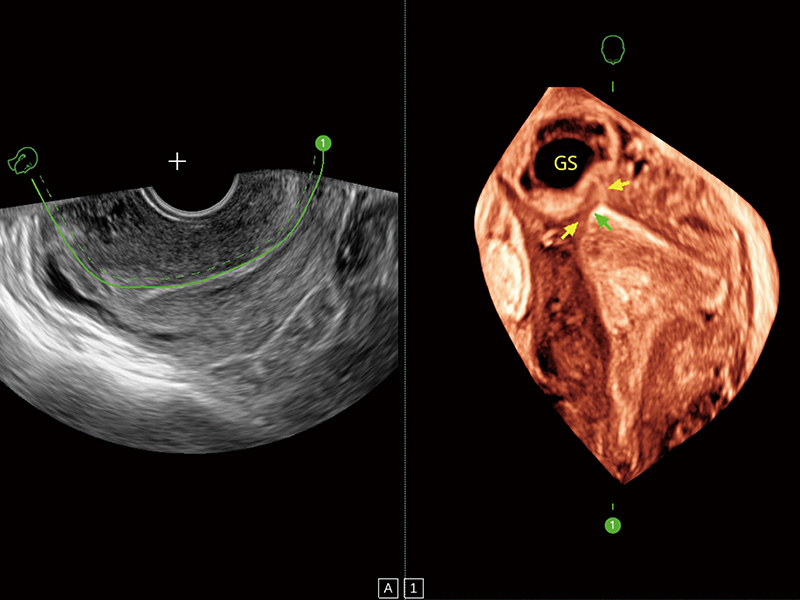

“生育问题”即关系民族复兴,也关系亿万家庭的幸福。随着婚育年龄推迟、社会压力增加等因素,越来越多人群也面临着“生不出、生不好”的问题。辅助生殖作为治疗不孕不育最有效的方法之一,也逐渐成为育儿新希望。而超声检查能为生殖需求人群的初诊评估提供宝贵的信息。 P20 Elite是哈哈体育官网匠心打造的一款生殖应用型彩超。她继承哈哈体育官网高端极光平台,突破性地将多款新型芯片及硬件模块进行整合,均衡了高端系统性能与小巧灵动机身。P20 Elite卓越的图像质量搭载专科探头,旨在为您提供全面的辅助生殖解决方案。

P20 Elite配备了丰富的生殖探头群和临床应用功能,在卵泡监测、穿刺取卵、胚胎移植、妊娠确认等领域,为生殖需求人群提供了新的临床机会,重新定义高端超声如何应用于生殖健康检查。